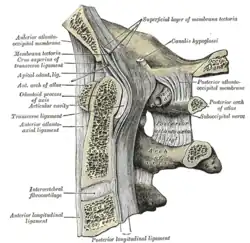

Median sagittal section through the occipital bone and first three cervical vertebrae (ligament of apex dentis labeled at center left as apical odontoid ligament) | |

The ligament of apex dentis (or apical odontoid ligament) is a ligament that spans between the second cervical vertebra in the neck and the skull. It lies as a fibrous cord in the triangular interval between the alar ligaments, which extends from the tip of the odontoid process on the axis to the anterior margin of the foramen magnum, being intimately blended with the deep portion of the anterior atlantooccipital membrane and superior crus of the transverse ligament of the atlas.